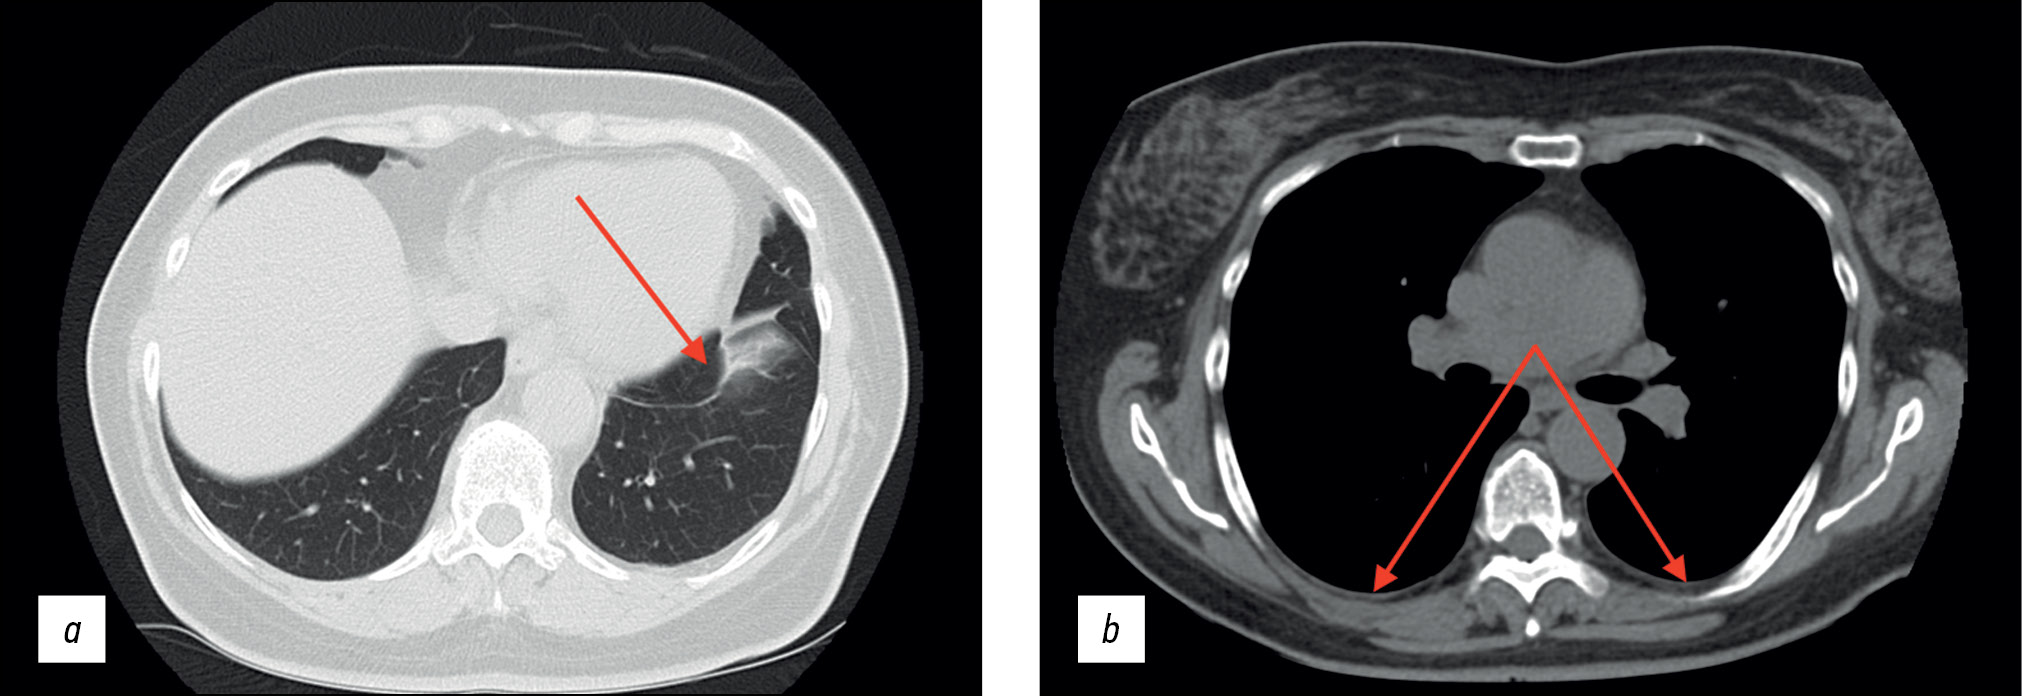

Upper gastrointestinal tract esophagogastroduodenoscopy revealed no abnormalities. A colonoscopy revealed erosive lesions of the descending colon, sigmoid, and rectum mucosa. The histology of the colon biopsy samples revealed catarrhal colitis. Abdominal CT with intravenous contrast (Figure 2) showed several abdominal lymph nodes (para-aortic and superior mesenteric lymph nodes, up to 10-mm short-axis diameter) during the patient’s stay in the Infection Department inpatient unit.

Fig. 2. Abdominal computed tomography scan with intravenous contrast (September 2020); axial plane: the red arrows show intraperitoneal lymph nodes.

The findings were classified as lymphadenopathy, and the patient was referred to a hematologist in September 2020. A bone marrow trephine sample was conducted, followed by histological examination; no indication of the hematopoietic system was identified. Compared with the earlier scan in August 2020 (see Figure 1), follow-up thoracic CT (Figure 3) revealed effusion resorption from the pleural cavities and partial regress of hypoventilatory changes in the basal parts of the lungs. Otherwise, no significant changes were found.

Fig. 3. Thoracic computed tomography scans (September 2020); axial plane: the red arrows show (a) the area with partial regression of the hypoventilation changes and (b) lack of pleural effusion.